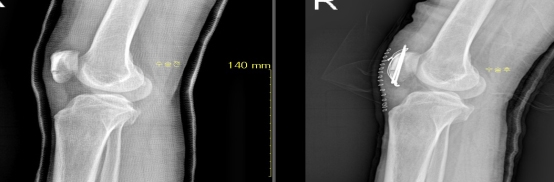

골절 및 탈구시에는 일반 방사선 촬영으로 확진하며 단순골절과 탈구의 경우에는 비수술적 치료방법으로 골절부위를 도수정복 후 석고 고정으로 치유할 수 있습니다. 그러나 도수정복 후에도 골절 부위가 이탈시 부전유합으로 진행되어 추후 어린이는 성장장애 및 외상 후 관절증을 유발시켜 장해에 이르기에 부득이 수술적 방법을 고려합니다. 본원은 최신식 이동형 C-ARM 영상장치를 이용하여 골절부위를 실시간으로 촬영하여 수술을 시행하고 있습니다.